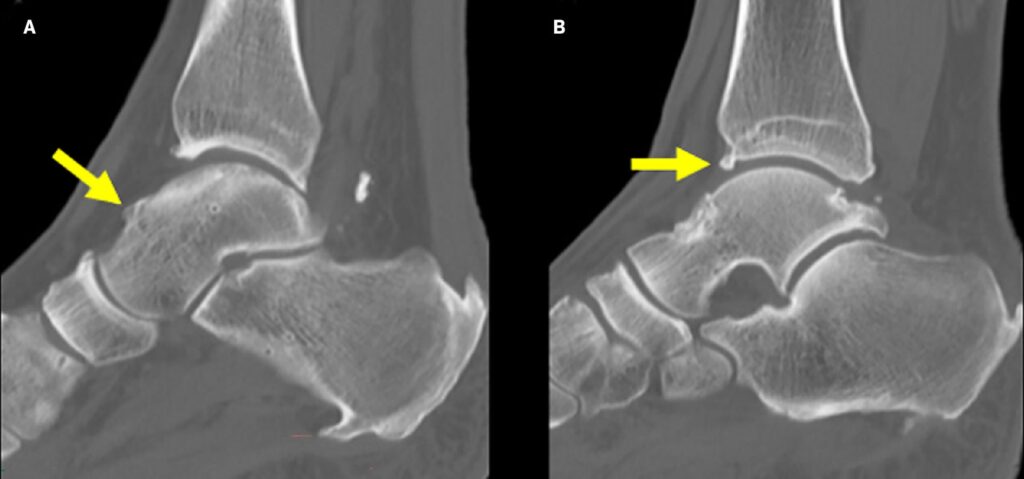

- Radiografie convenzionali: rappresentano l’indagine di primo livello, utili per identificare osteofiti tibiali e talari. Devono includere anche proiezioni in massima dorsiflessione: la più utile è l’obliqua craniocaudale a 45° con gamba ruotata esternamente di 30°11,12.

- TC: fornisce informazioni dettagliate su morfologia e posizione degli osteofiti, ed è utile nella pianificazione chirurgica32.

- RM: metodica più completa per le forme da tessuti molli; evidenzia sinovite, pliche, edema osseo, lesioni cartilaginee e instabilità associate11.